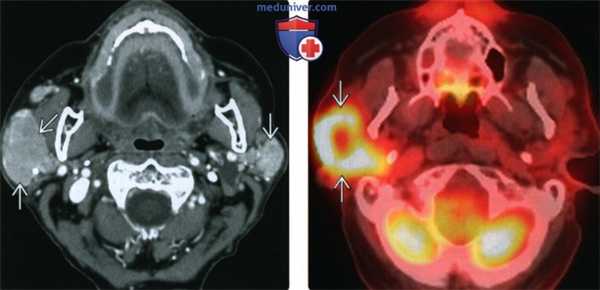

(Слева) КТ с КУ, аксиальная проекция. Двустороннее однородное увеличение околоушных желез с накоплением в них контрастного вещества. Диагноз - первичная лимфома у пациента с синдромом Шегрена. При первичной болезни Шегрена относительный риск возникновения лимфомы увеличивается в 13 раз. Данный случай представляет собой весьма типичный пример MALT-лимфомы околоушных желез.

(Справа) ПЭТ/КТ в аксиальной проекции, этот же пациент. Интенсивный захват ФДГ весьма характерен для лимфом. Интересно, что несмотря на то, что образование выглядит однородным, в его центре отмечается менее интенсивный захват ФДГ. Предположительно, это объясняется наличием центрального некроза.

(Слева) На аксиальной КТ с КУ у пациента с длительно существующим синдромом Шегрена определяется однородное контрастирование увеличенных околоушных желез с обеих сторон. У пациентов с синдромом Шегрена в 40 раз выше риск паротидной лимфомы, и это обычно лимфома MALT-типа.

(Справа) На аксиальной комбинированной ПЭТ/КТ определяется выраженное накопление ФДГ, типичное для лимфомы. На КТ опухоль выглядит однородной, но на ПЭТ/КТ в центре присутствует участок сниженного накопления ФДГ, позволяющий заподозрить некроз.